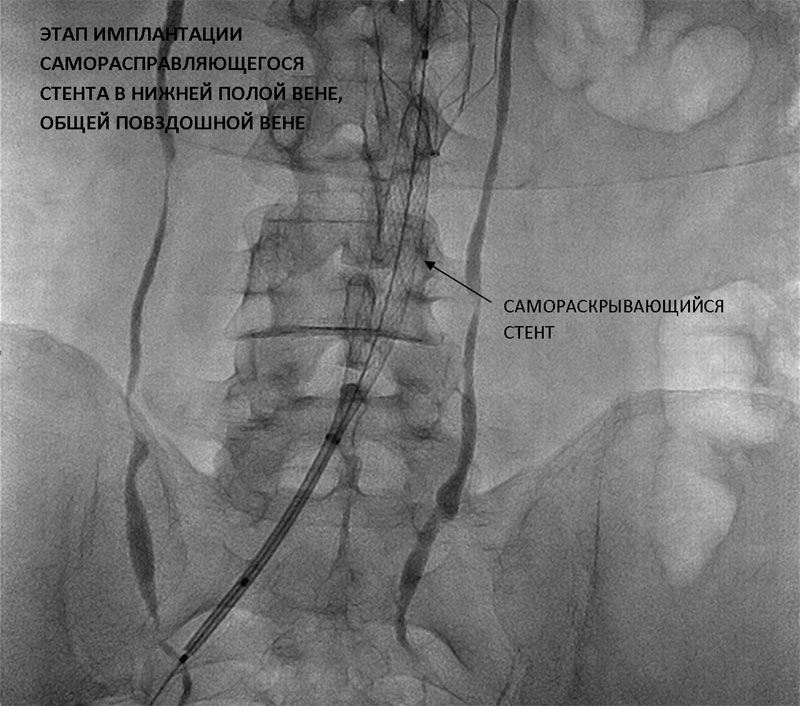

В Пироговском Центре успешно выполнена эксклюзивная операция — реканализация, ангиопластика, стентирование нижней полой вены и общей подвздошной вены слева.